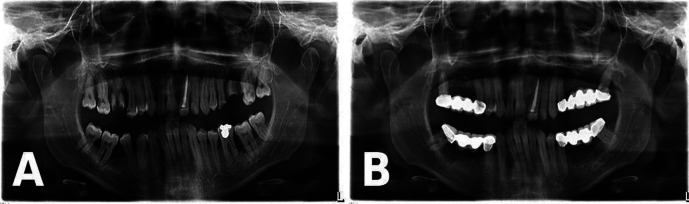

Congenital plasminogen (PLG) deficiency is an exceptionally uncommon hereditary disease associated with biallelic pathogenic / likely pathogenic variants in the PLG gene. Ligneous periodontitis (LP) is a rare disorder that can occur as a result of a lack of plasminogen. It is defined by the presence of lobulated, membranous, and ulcerated masses in the gums, as well as significant damage to the surrounding bone. This case report presents the diagnosis, treatment, and follow-up outcomes of a 23-year-old male patient who referred to our clinic with a complaint of widespread gingival enlargement. We identified a novel c.2087G>C (p.Arg696Pro) variant with a known variant detected in a compound heterozygous state in PLG confirming the molecular etiology. This case report emphasizes the importance of dentists identifying oral manifestations of various systemic diseases. Careful examination of such findings and the timely referral of patients to appropriate specialists for diagnosis and treatment are of critical significance. Key words:Ligneous periodontitis, plasminogen deficiency, genetic confirmation, histopathological diagnosis.